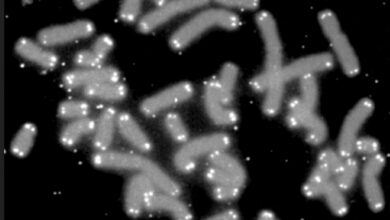

Así pues, los investigadores han encontrado que las AEC2 humanas (hAEC2), a diferencia de las AEC2 de ratón, se transdiferencian de manera robusta en células basales funcionales con señales de fibroblastos patológicos. El análisis de células individuales de la trayectoria de hAEC2 a células basales in vitro reveló la presencia de tipos de células de transición y subconjuntos de células basales previamente identificados en pulmones con fibrosis pulmonar idiopática (FPI).

Los autores, que han utilizado una plataforma organoide de fibroblastos/hAEC2, han modelado la metaplasia de células madre, o diferenciación anormal de células madre, observada en una lesión alveolar grave. Además, el descubrimiento de que las hAEC2 pueden generar tipos de células de transición patológicas y células basales proporciona una confirmación experimental de una trayectoria de células madre que se observa en los pulmones humanos enfermos.